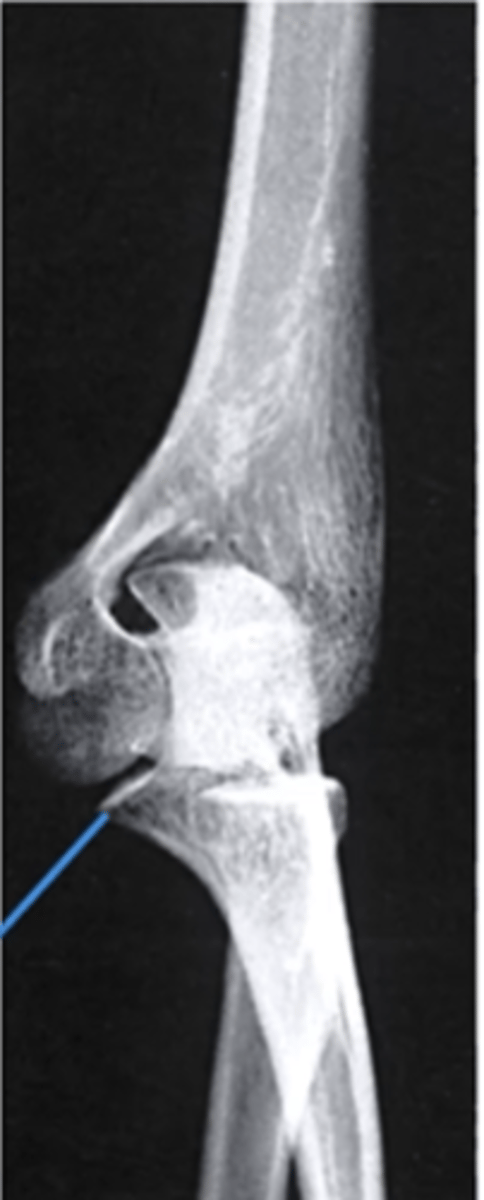

internal oblique elbow

what view is this

coronoid process

What does the blue line point to?